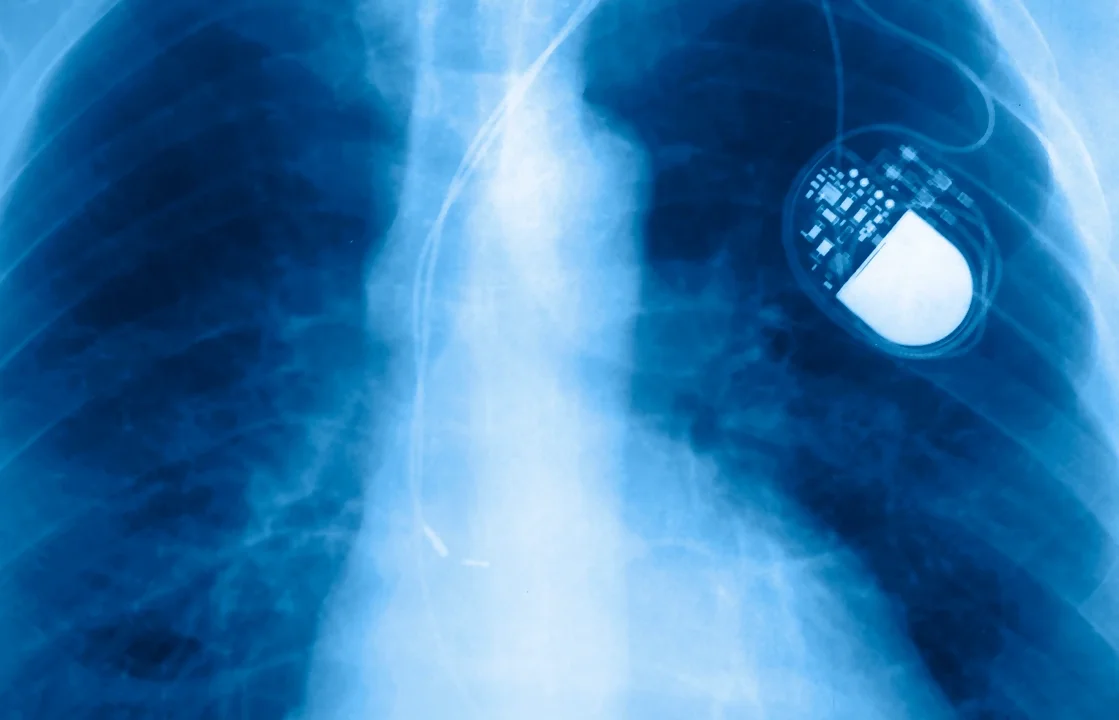

Radiografía del torso de una persona, donde se visualiza lo que es un marcapasos que se le ha colocado.

El marcapasos es un dispositivo que ayuda a regular el ritmo cardíaco en personas que presentan trastornos del sistema de conducción eléctrica del corazón o sistema de conducción cardíaco.

Su función principal es emitir impulsos eléctricos en momentos donde el corazón late demasiado lento o de forma irregular, esto ayuda a asegurar un ritmo cardíaco adecuado que permita mantener una circulación sanguínea eficiente.